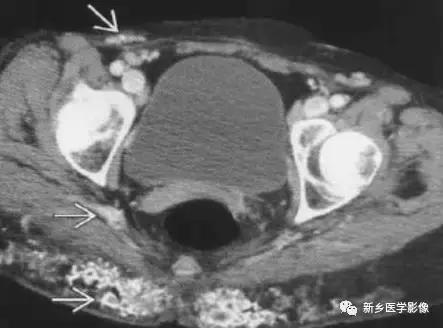

11、静脉石

12、钙化的肠系膜淋巴结

主要表现为腹腔内弥漫性的小的、多发的钙化,大小可不一致。